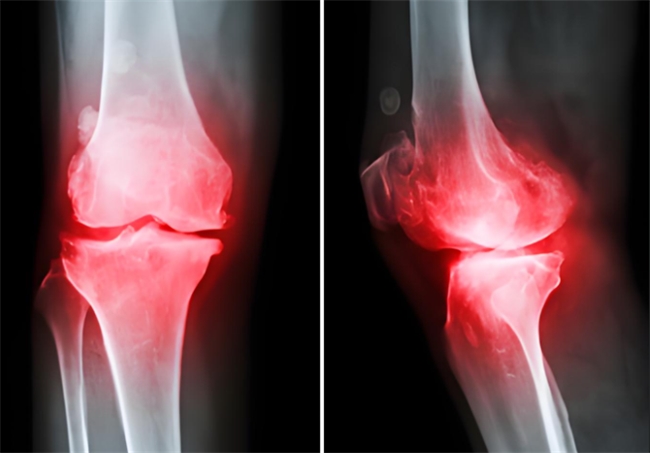

很多年轻人觉得,骨关节炎离自己很遥远,但实际上,骨关节炎从不是老年人的“专属”,年轻人也可能被它盯上。体重超标让关节长期承受超负荷压力,剧烈运动后的关节损伤、创伤后缺乏及时科学治疗,或是长期不良姿势、关节过度使用,都可能加速关节软骨的磨损与退化,进而引发骨关节炎。那么,罹患骨关节炎该如何治疗呢?氨糖就是常见的核心临床治疗药物。不过,它还分OTC硫酸氨糖和氨糖软骨素钙片,这二者又有什么区别,骨关节炎患者该选谁呢?

更关键的是,它缓解关节不适的效果,还得到了一项发布在世界顶级医学期刊《柳叶刀》的研究佐证:针对膝骨关节炎治疗,长期服用维固力,能让关节疼痛程度显著减轻约4倍[2],关节功能指数提升约2倍[3],还能加速合成关节软骨重要物质,将关节间隙变窄的速度延缓约4倍[4]。不只是缓解表面不适,抑制损伤,更能从根源改善关节结构,减缓磨损速度。